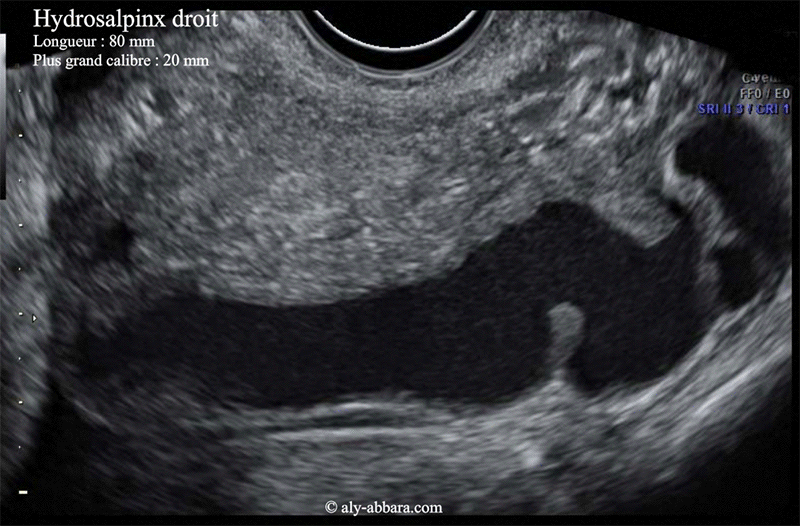

Hydrosalpinx droit

Image animée montrant un des aspects échographiques d'un volumineux hydrosalpinx droit

Cette pathologie tubaire a été mise en évidence chez une patiente souffrant d'une poussée aiguë d'infection génitale haute sur une infection génitale haute chronique avec la présence du côté controlatéral d'un abcès ovarien et d'un pyosalpinx.